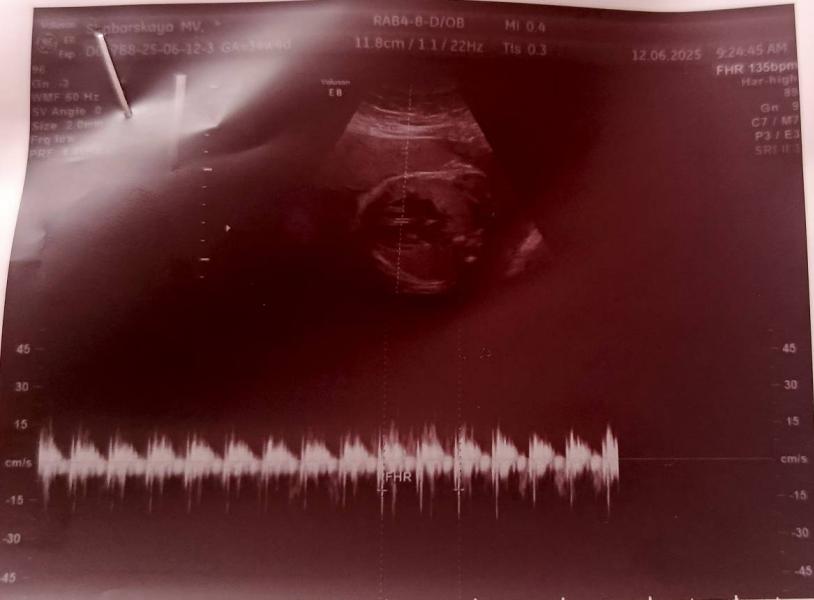

Вот и наступили 30 недель, как быстро они пролетели осталось чуть-чуть и мы встретимся с малышом. Сегодня ходила на 4д узи, но к сожалению получилось просто узи так как Малыш отвернулся от нас лицом))) Но главное что он здоров, вес прибавляет хорошо уже весит 1425+-208 гр, рост 38 см. Врач сказала что волосики на голове уже больше 1 см))